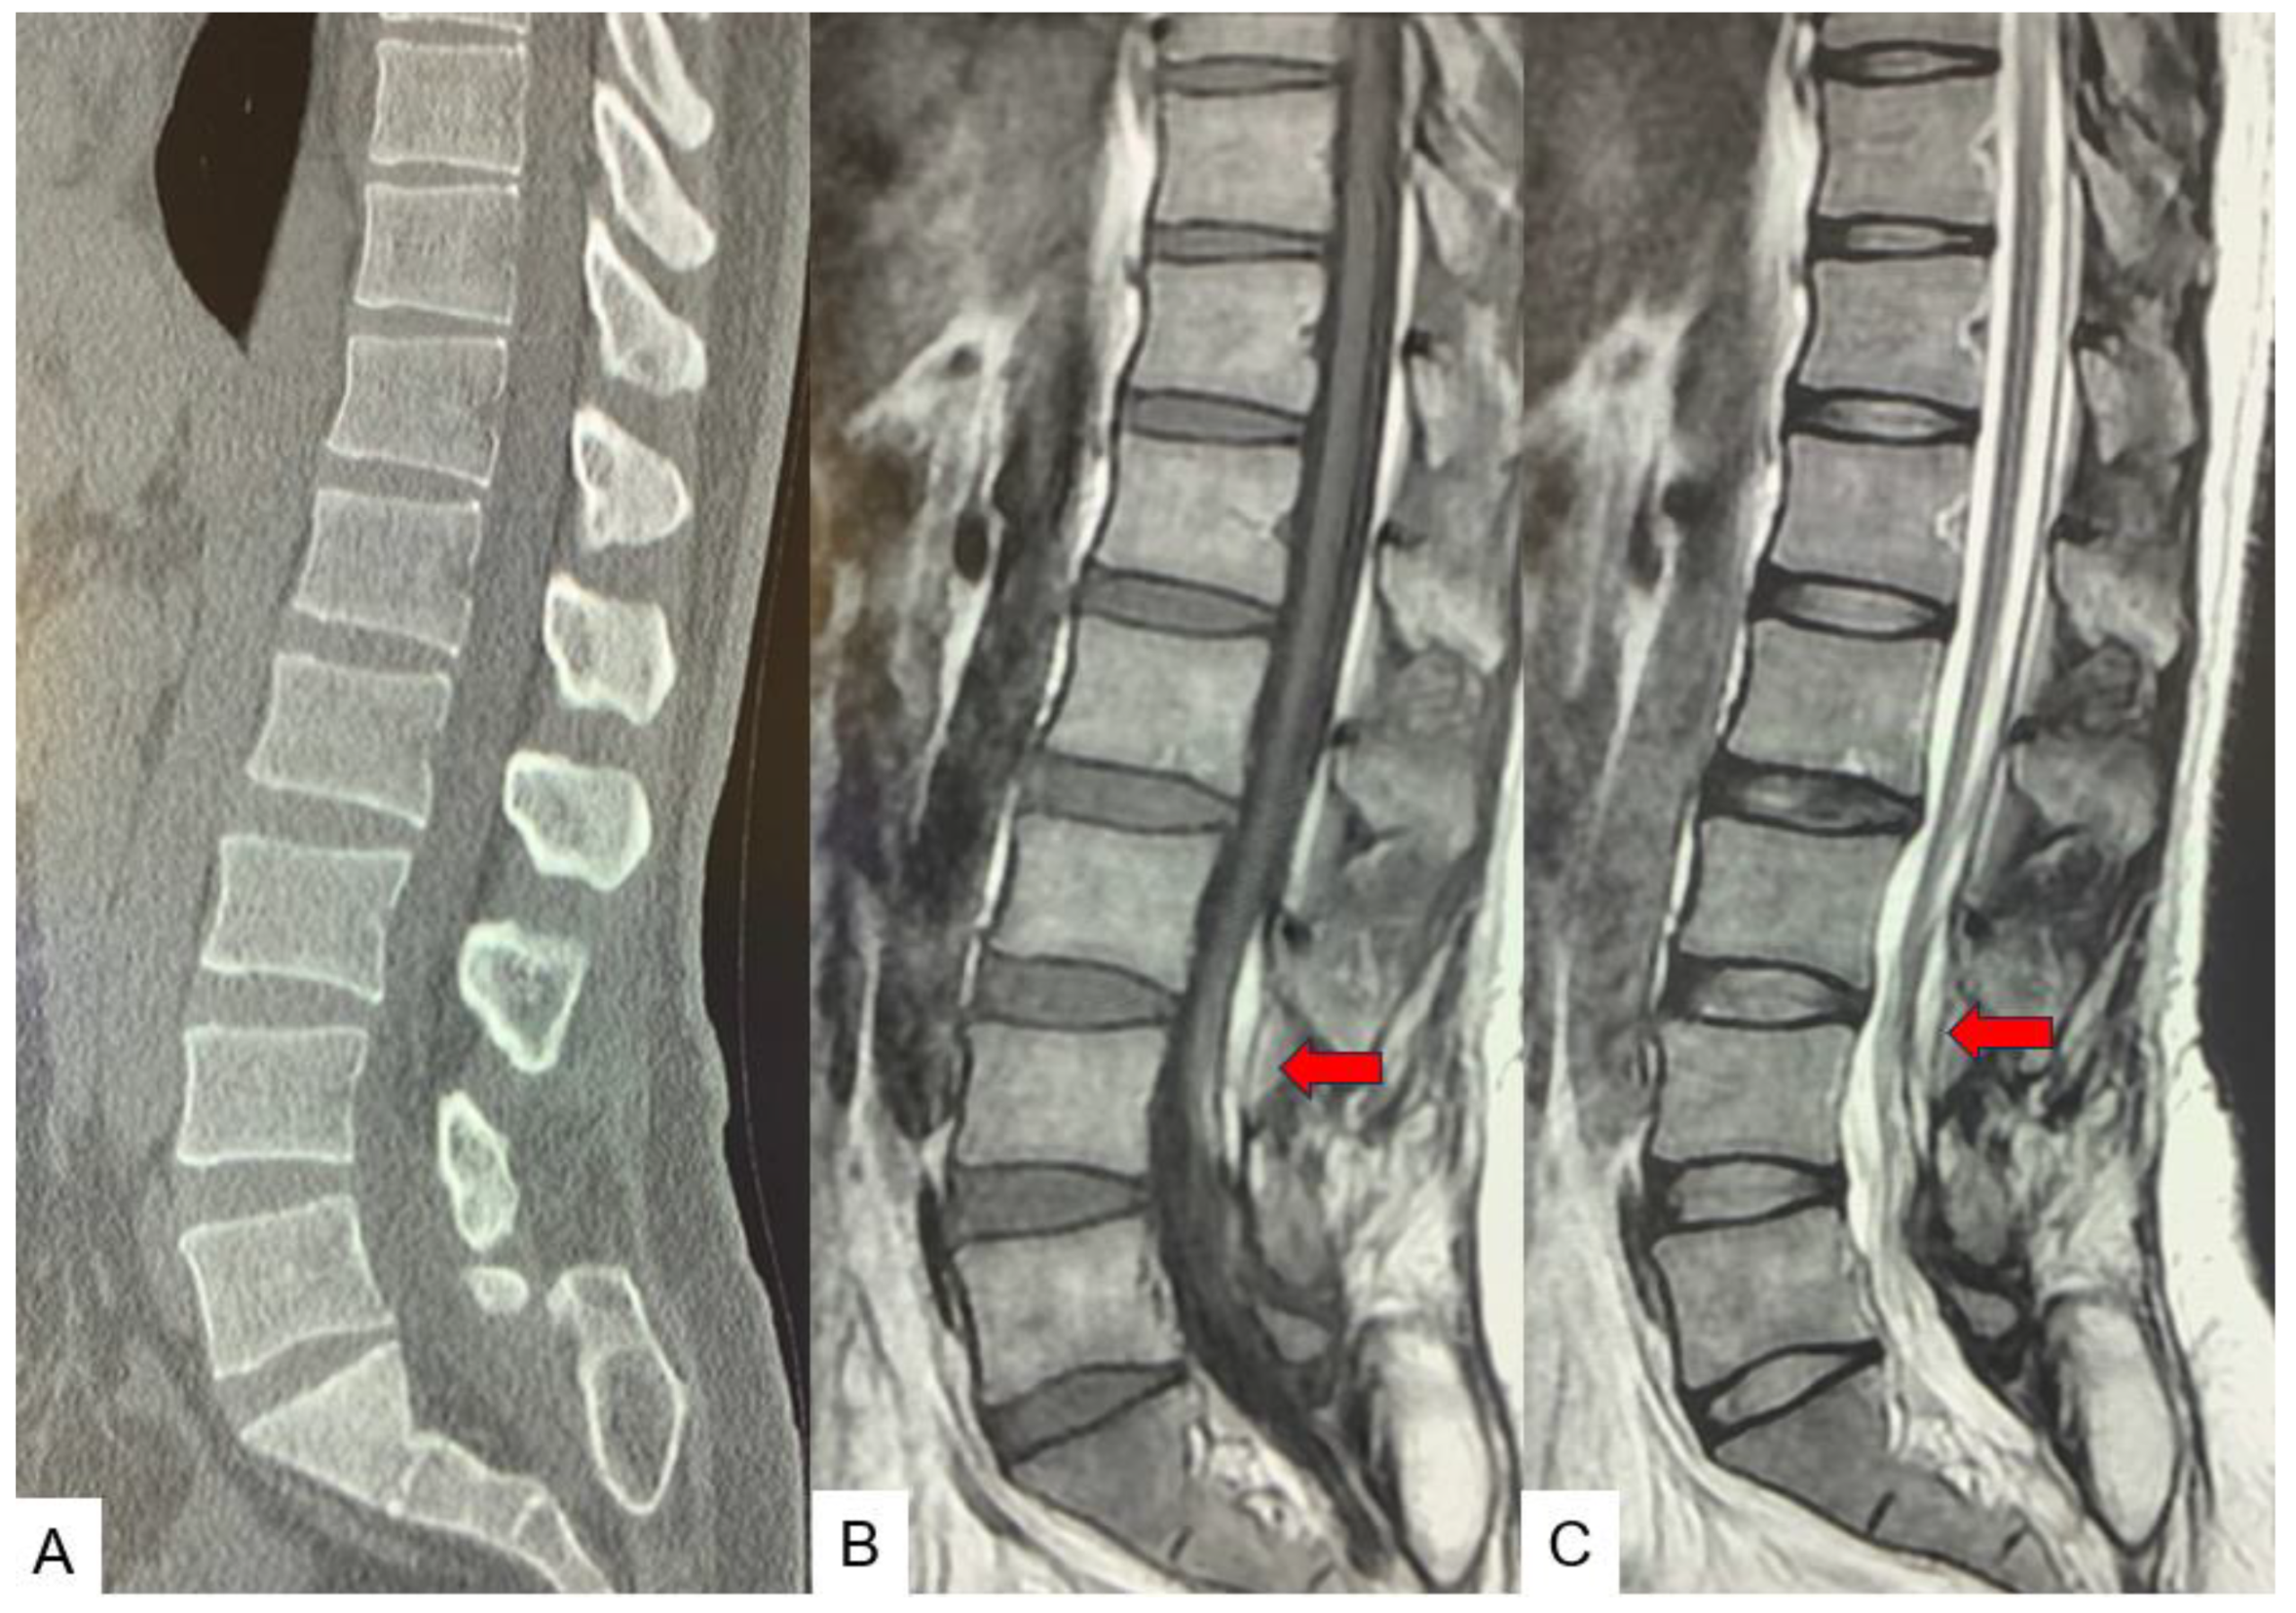

2.3. Preoperative imaging